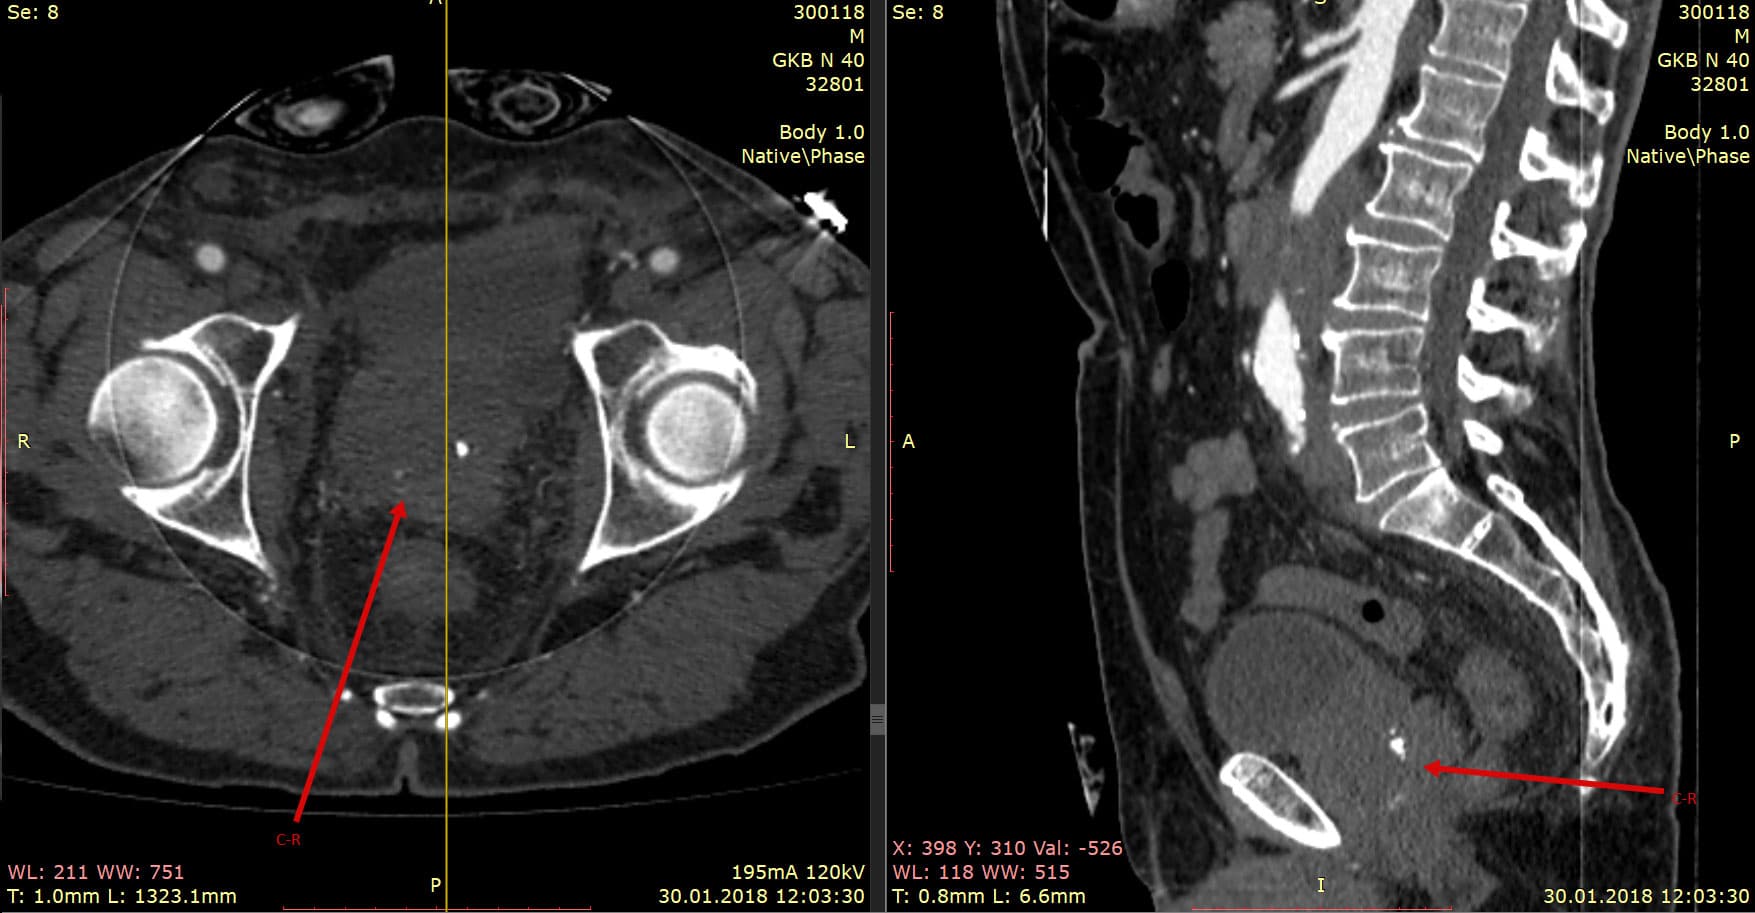

Компьютерная томография (КТ) грудной клетки является важным методом диагностики опухолей и других патологий легких и окружающих тканей. Это невероятно точное и информативное исследование, которое позволяет выявить заболевания на ранних стадиях и определить их характеристики.

С помощью КТ грудной клетки можно получить трехмерное изображение органов и тканей, что обеспечивает более детальное исследование, чем обычные рентгеновские снимки.

Одним из ключевых преимуществ КТ является возможность детектирования очень маленьких опухолей и изменений в тканях, которые могут остаться незамеченными на других видах обследований.

КТ также позволяет оценить степень распространения опухоли, наличие метастазов и возможные осложнения заболевания.

Благодаря КТ специалисты могут более точно определить тактику вмешательства и выбрать оптимальный способ лечения для каждого конкретного случая.